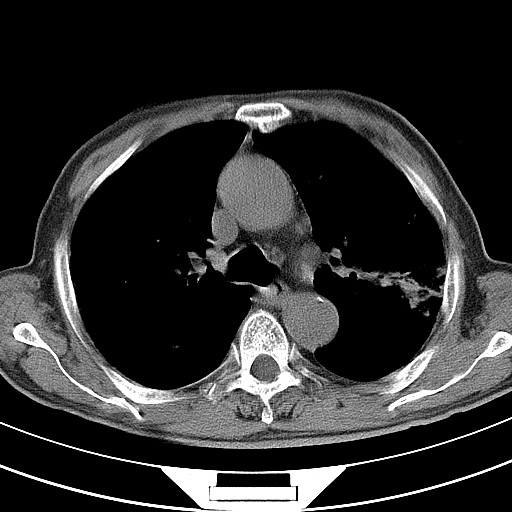

男,71岁,糖尿病住院,无发热、咳嗽、咳痰。

肺气肿,右肺下叶感染。左肺空洞。并与血管连接不排除周围型肺癌。

1.左肺结核伴空洞形成

2.双肺下叶炎症

支持结核,建议痰菌检查;左侧上叶间隔旁型肺气肿

1)两肺感染性病变(结核可能性大)。2)左肺上叶近纵隔胸膜下肺大泡。

两肺感染性病变(结核可能性大,有空洞形成)。

1)两肺继发性结核。2)左肺上叶近纵隔胸膜下肺大泡。